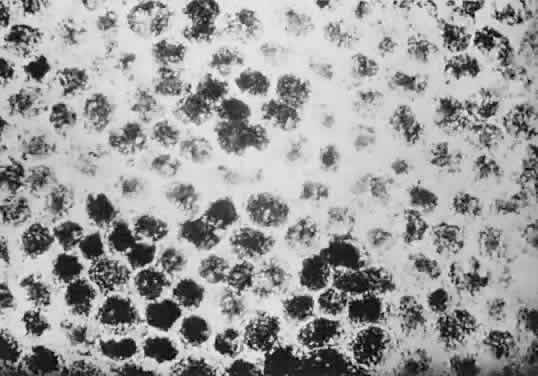

Histologically, congenital hypertrophy of the RPE is characterized by a monolayer of large RPE cells containing larger-than-normal pigment granules (Fig. 19; see Fig. 18B through E). Overlying photoreceptor elements have been shown to be degenerated, which explains the localized visual field defects corresponding to these areas.170

Fig. 19. A. Electron microscopic findings of normal-appearing retinal pigment epithelium (RPE) granules. B. Electron microscopy within area of congenital hypertrophy of the RPE shows enlarged pigment granules and a thickened basement membrane (bm) of the RPE cells. (Buettner H: Congenital hypertrophy of the retinal pigment epithelium. Am J Ophthalmol 79:177, 1975)

Histologically, the involved RPE cells are taller and contain a greater concentration of pigment granules (which may be enlarged) than normal RPE (Fig. 21). The overlying retina has been shown to be unaffected in one patient.171

Fig. 21. Flat-mount preparation of congenital grouped pigmentation of the retina shows a greater concentration of pigment granules within the area corresponding to the lesions. (Courtesy of Dr. Jerry Shields)